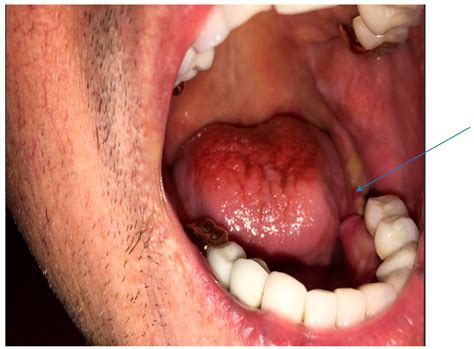

Identifying a jaw bone infection early is crucial for preventing permanent bone damage. Symptoms can vary in intensity depending on the stage of the infection. Patients should monitor for the following warning signs:

• Persistent, throbbing pain in the jaw or facial area.

• Visible swelling of the gums, cheek, or jawline.

• Formation of a sinus tract (a small pimple-like bump on the gum that may release pus).

• Difficulty opening the mouth or experiencing “lockjaw.”

• Fever and general malaise, indicating a systemic reaction.

• Bad breath (halitosis) or a persistent metallic/foul taste in the mouth.

• Numbness in the lips or chin due to inflammation pressing on nerves.